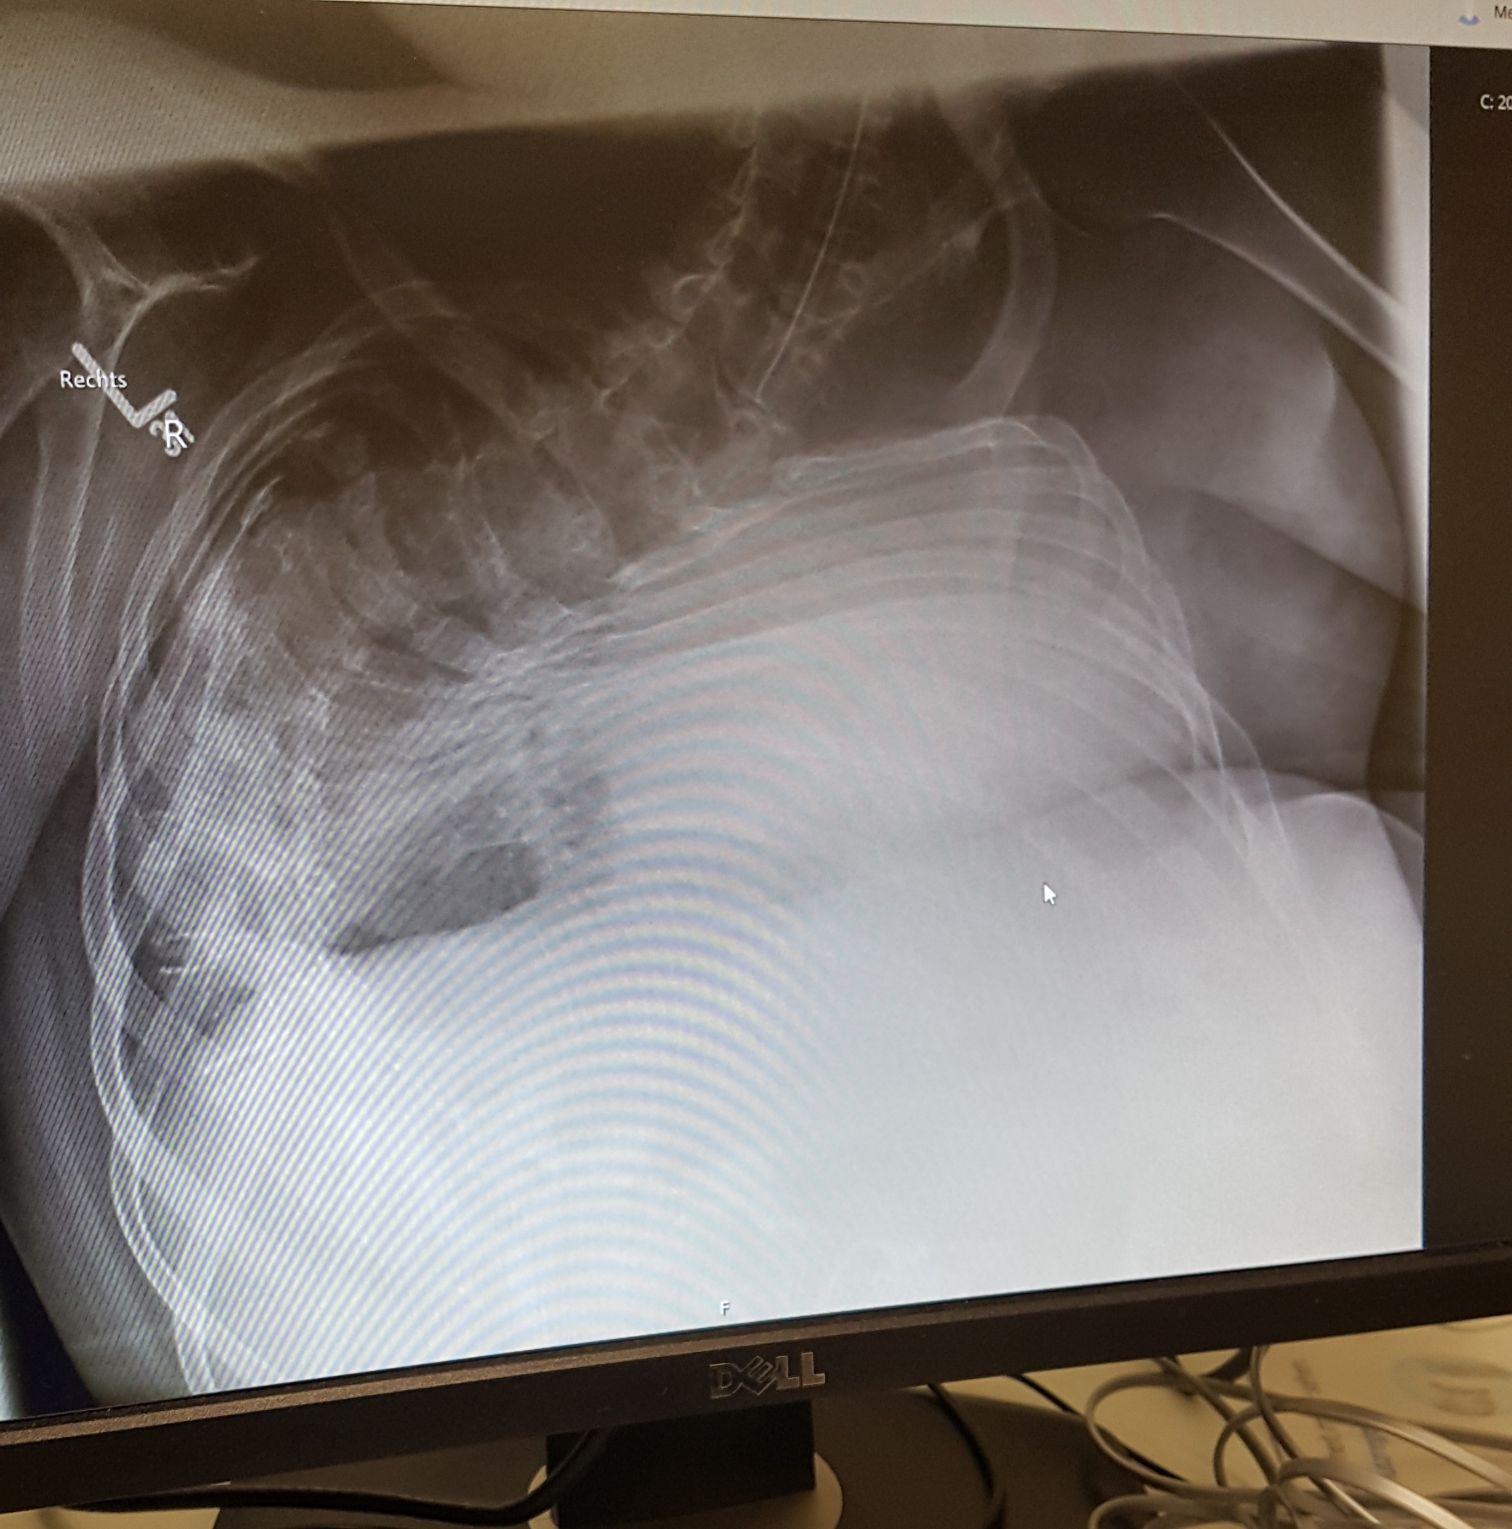

CR of a 14 y Boy in ICU

Radiology

Diagnostic

Whatsyourdiagnosis